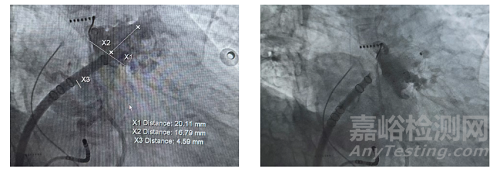

左心耳解剖:DSA 造影顯示心耳為 “典型菜花型”(分葉多、內(nèi)部結(jié)構(gòu)復(fù)雜),口徑 16mm,深度 25mm—— 小口徑心耳需精準(zhǔn)選擇器械尺寸,避免過(guò)度壓縮導(dǎo)致心耳壁損傷。

2. 手術(shù)操作過(guò)程

器械選擇:選用20mm 規(guī)格 WATCHMAN FLX Pro,依據(jù) RO Marker 確認(rèn)器械在分葉間的位置,確保封堵器邊緣完全覆蓋心耳開(kāi)口。

釋放與評(píng)估:釋放后通過(guò)DSA 觀察,3 個(gè) RO Marker 呈 “等邊三角形” 分布,提示器械軸向正常;TEE 評(píng)估顯示瓣周漏<1mm,封堵效果符合臨床標(biāo)準(zhǔn)。

全球首款,波科涂層左心耳封堵器獲批上市

▲術(shù)前左心耳造影(左);封堵器展開(kāi)后TEE影像(右)

3. 術(shù)后專家反饋

姚焰教授在術(shù)后總結(jié)中提及:“3 個(gè) RO Marker 讓術(shù)中釋放非常順利,能清晰展示封堵器軸向是否偏移 —— 這對(duì)小口徑心耳尤為重要,避免了因定位偏差導(dǎo)致的二次調(diào)整。更關(guān)鍵的是,PVDF-HFP 涂層帶來(lái)的快速內(nèi)皮化,我們期待 3 個(gè)月隨訪時(shí)能看到完整的內(nèi)皮覆蓋,為患者停用抗凝藥提供依據(jù)。”